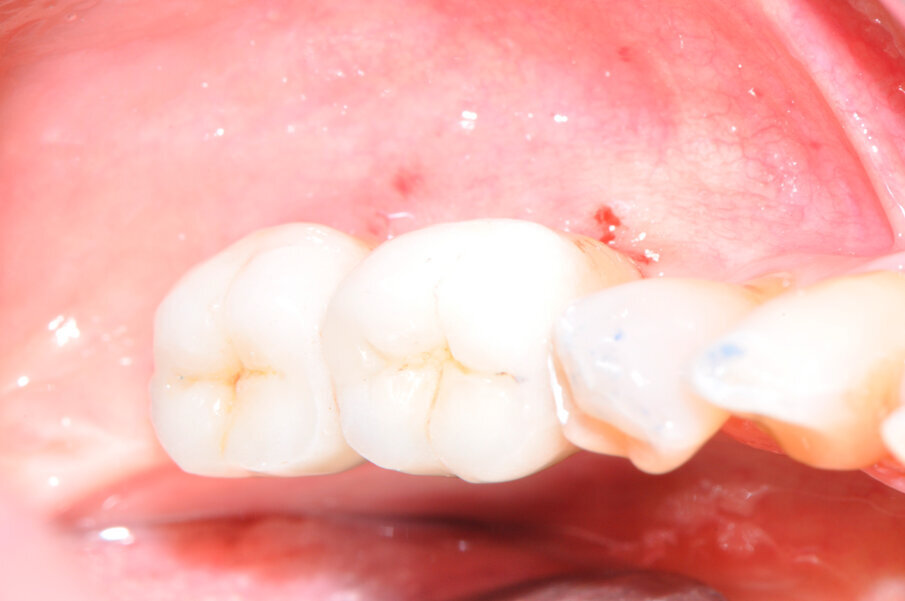

La paziente forniva il proprio consenso informato. La paziente è stata sottoposta 5 giorni prima dell’intervento a una igiene orale professionale al fine di risolvere la condizione infiammatoria relativa alla mucosa e predisporre la zona perimplantare all’intervento per la rigenerazione ossea, ottenendo uno stato ottimale dei tessuti molli, compatibilmente con la patologia in atto (Fig. 2). Si è prescritta una terapia antibiotica con amoxicillina/acido clavulanico (Augmentin, Glaxo-SmithKline, Verona, Italy) tre giorni prima della chirurgia ogni 12 ore e per i successivi 8-10 giorni. In seguito alla seduta di igiene pre-intervento, la paziente è stata anestetizzata localmente con articaina 1:100.000 per procedere alla fase chirurgica.

Fig. 2 – Aspetto clinico delle mucose perimplantari al momento dell’atto chirurgico.